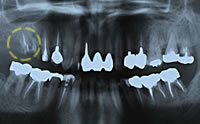

治療前

治療前のパノラマX線写真パノラマX線写真